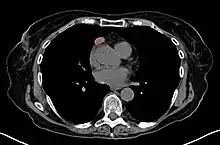

Imaging

A chest X-ray may identify widening of the mediastinum suggestive of thymoma, but computed tomography or magnetic resonance imaging (MRI) are more sensitive ways to identify thymomas and are generally done for this reason.[43] MRI of the cranium and orbits may also be performed to exclude compressive and inflammatory lesions of the cranial nerves and ocular muscles.[44]

As thymomas are seen in 10% of all people with the MG, they are often given a chest X-ray and CT scan to evaluate their need for surgical removal of their thymus glands and any cancerous tissue that may be present.[23][42] Even if surgery is performed to remove a thymoma, it generally does not lead to the remission of MG.[62] Surgery in the case of MG involves the removal of the thymus, although in 2013, no clear benefit was indicated except in the presence of a thymoma.[68] A 2016 randomized, controlled trial, however, found some benefits.[69]